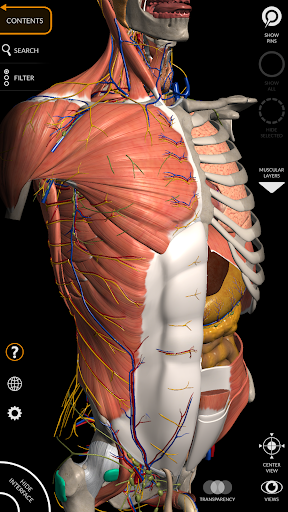

"Anatomy 3D Atlas" vous permet d'étudier l'anatomie humaine de manière simple et interactive.

Grâce à une interface simple et intuitive, il est possible d'observer chaque structure anatomique sous n'importe quel angle.

Les modèles anatomiques 3D sont particulièrement détaillés et avec des textures jusqu'à une résolution de 4k.

La subdivision par régions et les vues prédéfinies facilitent l'observation et l'étude de parties individuelles ou de groupes de systèmes et les relations entre différents organes.

• Système musculo-squelettique

• Système cardiovasculaire

• Système nerveux

• Option pour masquer ou isoler un ou plusieurs modèles sélectionnés

• Filtrez pour masquer ou afficher chaque système

• Visualisation des muscles à travers des niveaux de couches depuis les plus superficielles jusqu'aux plus profondes